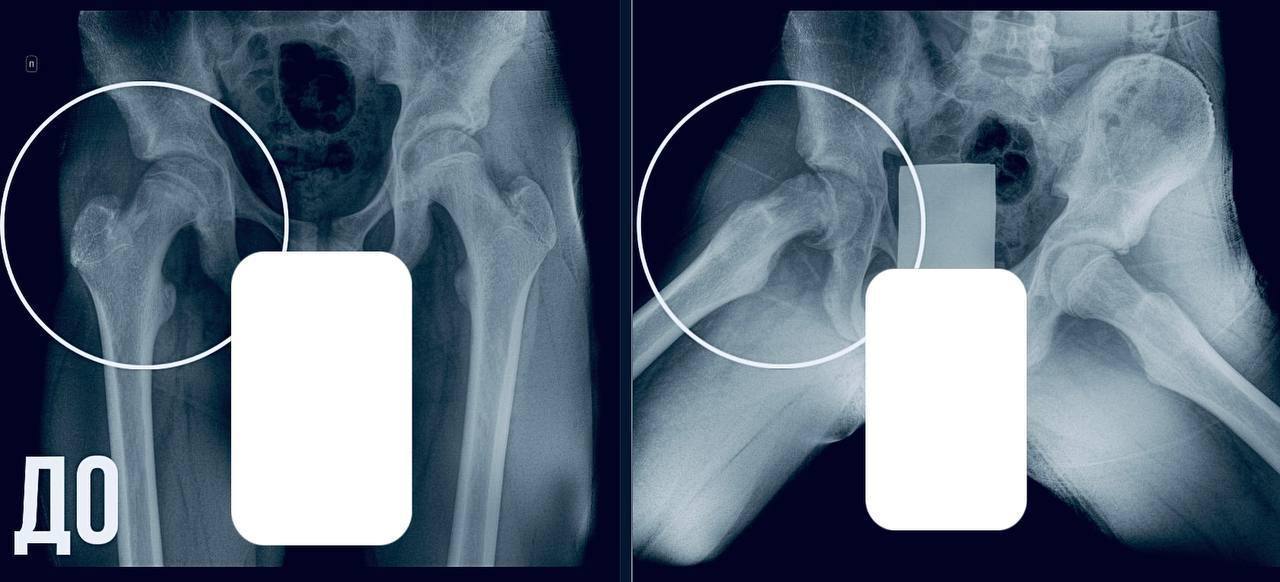

В МОДКТОБ обратились родители 13-летнего мальчика: у него болело бедро, появилась хромота и неустойчивая походка. Обследование показало юношеский эпифизеолиз — смещение головки бедренной кости в период активного роста.